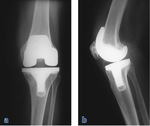

Osoby ze zmianami zwyrodnieniowymi stawów (głównie w zakresie stawu kolanowego i biodrowego) stanowią jedną z największych grup pacjentów kliniki. Jej szef zwraca uwagę, że coraz więcej pacjentów to ludzie młodzi, zwykle uprawiający sporty ekstremalne, u których do zwyrodnień doszło na skutek urazów. Nadal jednak większość to osoby powyżej 60. r.ż., a więc w wieku, w którym najczęściej dochodzi do rozwoju artrozy. W początkowej jej fazie leczenie polega na stymulowaniu wzrostu tkanki chrzęstnej poprzez stosowanie fizykoterapii oraz podawanie (doustnie lub poprzez wstrzykiwanie do stawu) preparatów wzmacniających chrząstkę lub aktywujących w niej procesy naprawy. Na przykład do stawu wprowadza się preparaty zawierające składniki chrząstki stawowej, takie jak siarczan chondroityny i kolagen, osocze bogatopłytkowe zawierające czynniki wzrostu, hialuronian sodu, tzw. kwas hialuronowy, czy komórki macierzyste. W IV stopniu zwyrodnień, gdy dochodzi już do odsłonięcia kości, która w dużej części przestaje być pokryta tkanką chrzęstną, takie działania są już niewystarczające i pozostaje chirurgiczne „wycięcie” stawu oraz zastąpienie go wszczepioną endoprotezą (ryc. 1). Z piśmiennictwa światowego wynika, że w 2005 roku wszczepiono na świecie 532 tys. endoprotez kolana, a szacowany jest blisko siedmiokrotny wzrost liczby tych operacji w 2030 roku do 3 mln 480 tys.